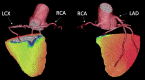

Case summary: We describe a 34-year-old man with a history of a single episode of chest pain. An ectopic origin on the part of the left circumflex (LCX) coronary artery from the proximal right coronary artery (RCA) was evident upon coronary computed tomography angiography. A positron emission tomography perfusion study revealed a stress-induced perfusion defect in the anomalous LCX territory (infero-posterior wall). The patient experienced dyspnoea and ST-segment depression in electrocardiography, suggestive of myocardial ischaemia during the maximal bicycle ergometer stress test. No mechanical compression or stenosis was seen upon invasive coronary angiography. The left ventricular perfusion normalized after the initiation of beta-blocker medication.

Discussion: Patients with CAAs especially benefit from a multimodality assessment of the vascular territories. In our case, the myocardial perfusion of the infero-posterior wall normalized after treatment with beta-blockers. This may be due to increased coronary vasodilation capacity and myocardial flow reserve, as well as reduced oxygen consumption. Beta-blockers may represent a viable option in low-symptomatic CAA patients with perfusion defect and no ostial stenosis or compression.